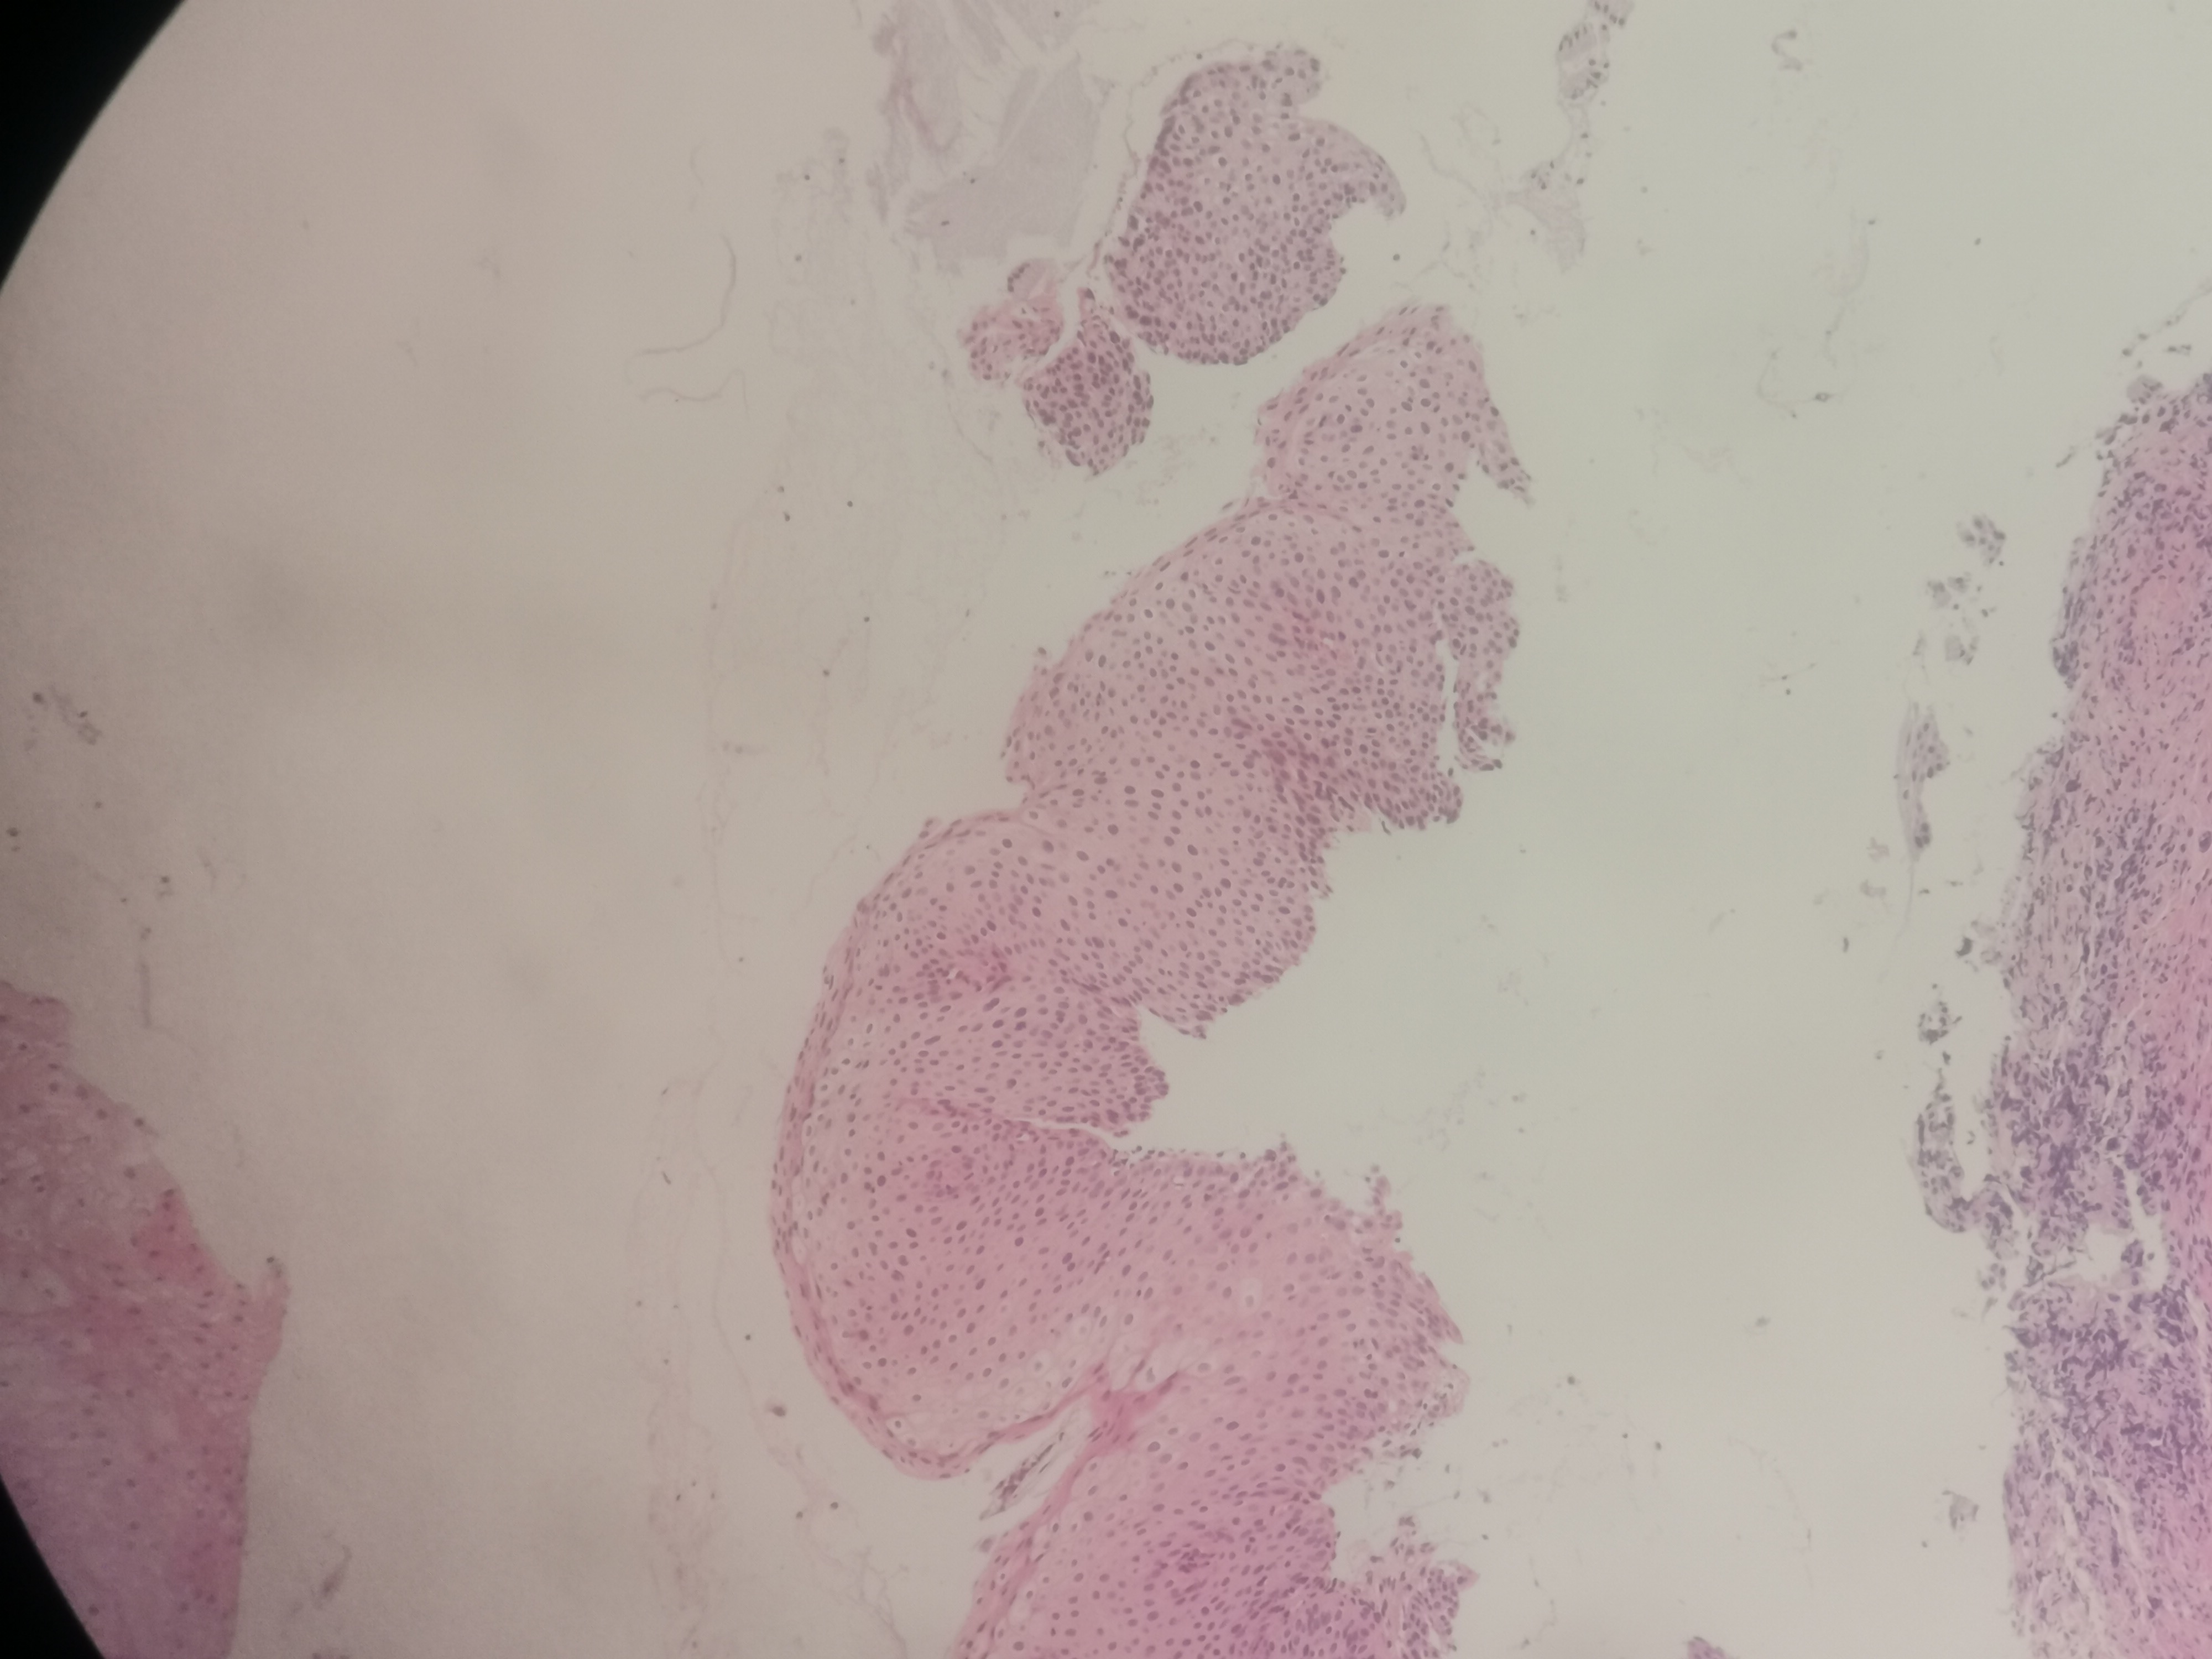

急!请老师帮忙看看,12点够CINii吗,还是报CINI~II

性别

女

年龄

59岁

临床诊断

HPV感染

一般病史

HPV16(+)

标本名称

宫颈活检组织

大体所见

3点:0.8x0.4x0.3厘米1块。6点0.7x0.6x0.3厘米1块。9点0.6x0.6x0.4厘米1块。12点0.8x0.5x0.3厘米,0.6x0.6x0.4厘米2块。

图1~16为12点2块组织,图17为9点组织,图18,为6点组织,图19为3点组织。

图1

倾向低级别,标记看看